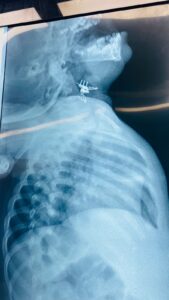

وأوضحت الطبيبة الاختصاص جراحة الأنف والأذن والحنجرة الدكتورة فرقان حميد محمد” أن الطفلة أُدخلت إلى صالة عمليات الطوارئ وهي تعاني من اختناق وسعال شديدين وعلى الفور تم إجراء الفحوصات والأشعة اللازمة التي أظهرت وجود جسم غريب في مدخل المجرى التنفسي.